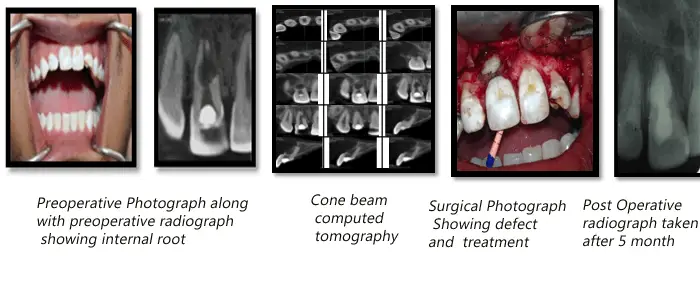

Perforating Internal Resorption

In this case, the patient came with chief complaint of pain in the upper front teeth, on oral examination, the teeth morphology appeared normal, however radiographic examination revealed internal root resorption in relation to 11; further investigations were carried out using the cone beam computed tomography (CBCT) to reveal the extent of the defect and thereby chart the treatment and prognosis of the affected tooth; treatment plan included filling of the defect with glass ionomer cement and sealing the root apex using MTA(Mineral trioxide aggregate), post endodontic therapy.